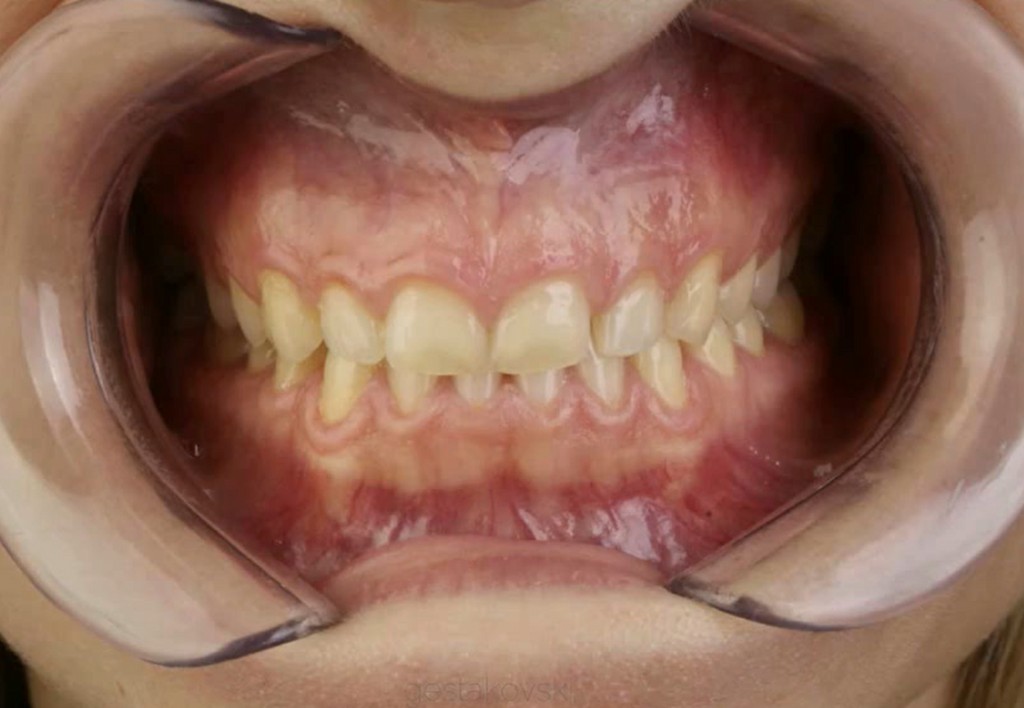

► Analisi funzionale e relazione centrica

► Progettazione occlusale funzionale

Galleria fotografica